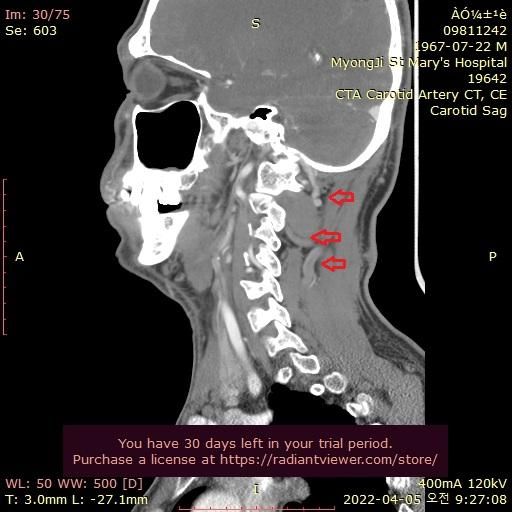

그런데 가까운 의원에서 그때의 영상을 보다가 그림과 같이 목 뒤쪽에 정맥혈관에 기형이 심한것을 알았습니다.

울퉁불퉁 하고 아주 굵어져서 혈액 순환이 안도는것으로 보입니다.

자료 찾아보니 심부경정맥 인것 같습니다. 내경정맥등과 함께 뇌의 혈액을 심장으로 빼내서 보내주는 중요한 혈관으로 보입니다.

기형이 심해서 혈액이 잘 안 빠지는 것일까요?

1. 목 부위 경동맥과 추골동맥등 CTA찍으면 잘 나오던데, 왜 경정맥과 심부경정맥등 정맥은 영상을 안찍나요?

동액 사진만 있지, 정맥은 사진이 전혀 없네요.

2. 목 부위 정맥을 찍으면 목뒤 심부경정맥등 모두 잘보이게 찍을수 있는 방법이 있나요? 그렇다면 저 기형인가 변형인가 잘 보일텐데요.